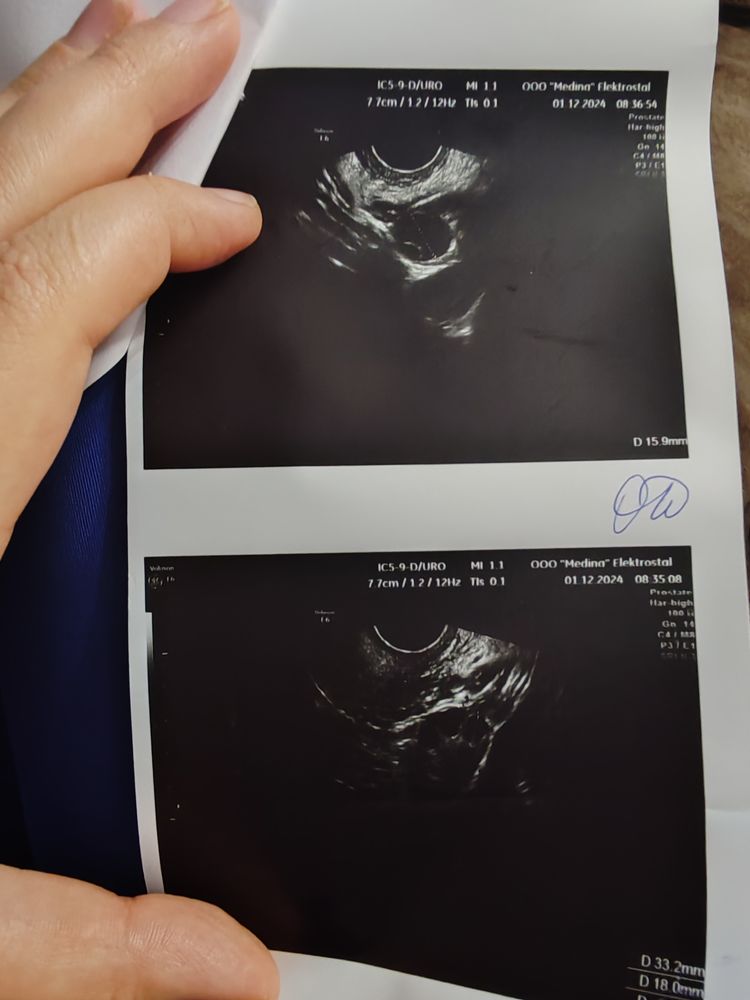

Результаты УЗИБыла стимуляция летрозолом. УЗИ контроль и в чт намеряла узистка дф 17 мм, в субботу укололи овитрель, т.е вчера.

И сегодня шок. Была на УЗИ в правом пя Два дф 16 мм, один с яйценосным бугорком. Неужели они теперь не лопнут? Неужели сдуются из-за ошибки узистка.

Наталья, здравствуйте! А у вас остались снимки прошлого УЗИ и этого? Я сама работаю на УЗИ , интересно сравнить как вам так измерили по разному (

Ольга, могу даже фото скинуть где чётко 2 фолликула, и на одном яйценосный бугорок. Второй бы так быстро не вырос

Наталья, посмотрела. Если честно разницы особой между первым и вторым фото не увидела. Разница в 1-2 мм это норма. Даже в один день могут так измерить. Тут вопрос в другом , почему фолликул с чт до вскр не вырос совсем. И по фото к сожалению не очень понятно на счет второго доминантного фолликула. На первом фото четко видно один. На фото с вскр я если честно тоже вижу только один фолликул. Что под ним внизу по фото не понятно. Надо смотреть в живую. Раз есть бугорок по идее должен лопнуть. Вопрос только будет ли он достаточно созревшим( И увидела что эндометрий маловат. Принимаете что то из эстрогенов для эндометрия ?